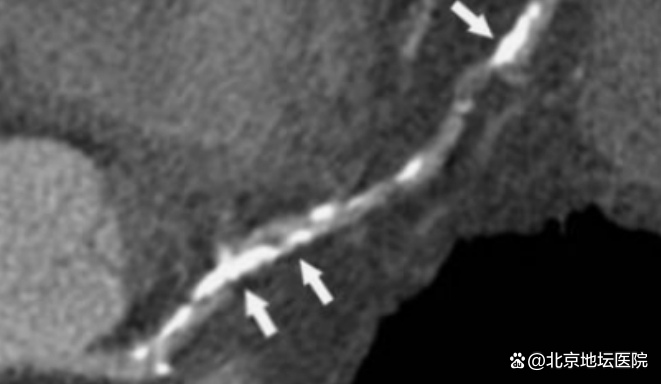

白色部分为钙化的“硬石头”

陈大爷冠脉造影后进一步完善了OCT检查结果提示:右冠脉中段开始弥漫性纤维钙化斑块形成,局部呈环形钙化,最小管腔面积仅2.6mm²,导丝无法到达血管远端,更换导丝后到达血管远端,但不能充分预扩张,应用传统的切割球囊处理后仍无法达到满意的预处理效果。心内科管浩副主任带领冠脉介入小组经过对患者冠脉情况的充分评估讨论,最终决定使用Shockwave冲击波球囊对患者进行治疗。